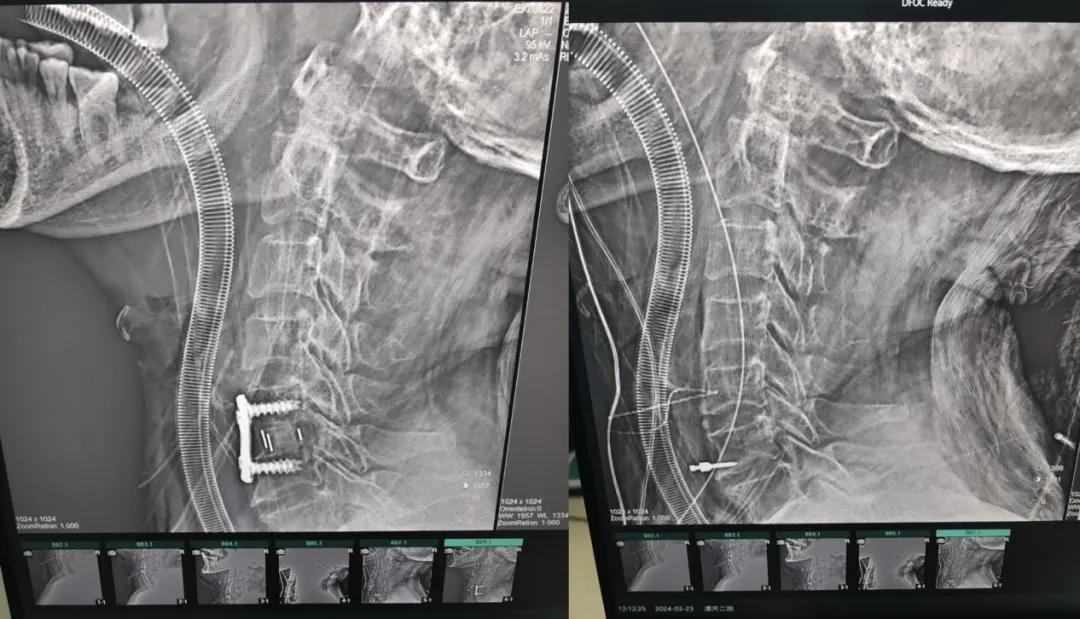

近日,70歲的馬阿姨,因摔傷后出現(xiàn)持續(xù)性頸部疼痛伴右側(cè)肢體無(wú)力、麻痛,影響日常生活。于是來(lái)到市二院神經(jīng)外科就診,經(jīng)檢查發(fā)現(xiàn):頸椎MR示:頸3/4、4/5、5/6、6/7椎間盤變性突出(中央型)并繼發(fā)性椎管變窄,頸椎退行性改變,頸5椎體水平頸髓水腫。神經(jīng)外科副主任劉沛濤根據(jù)患者癥狀、體征、影像學(xué)三者結(jié)合診斷為“脊髓型頸椎病”,考慮到患者癥狀逐漸加重、保守治療效果不佳等情況,建議盡快手術(shù)治療。

經(jīng)過(guò)縝密的術(shù)前準(zhǔn)備和手術(shù)計(jì)劃,在鄭大一附院神經(jīng)外科張風(fēng)江教授的指導(dǎo)下,神經(jīng)外科團(tuán)隊(duì)順利為患者實(shí)施“顯微鏡下頸椎前路C5/C6椎間盤切除椎間融合+內(nèi)固定術(shù)”,手術(shù)時(shí)間不到1小時(shí)。術(shù)后患者恢復(fù)情況良好。